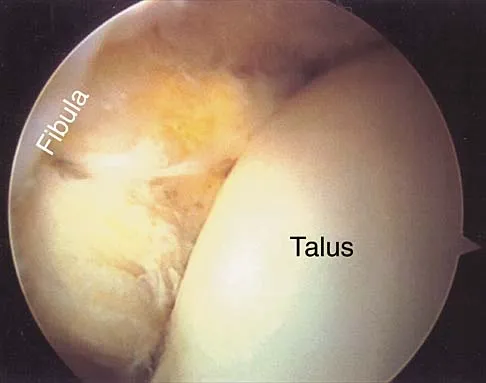

Figures 5a and 5b show axial and coronal MRI images of the left ankle of a patient with lateral ankle pain. What is the most likely diagnosis?

The figures show a longitudinal split within the peroneus brevis tendon as it courses posterior to the fibula. The peroneus longus tendon has been driven between the medial and lateral components of the peroneus brevis tendon. Peroneal split syndrome is a cause of lateral ankle pain but may be less asymptomatic in the elderly. It may be associated with tendon subluxation following a tear of the superior peroneal retinaculum.